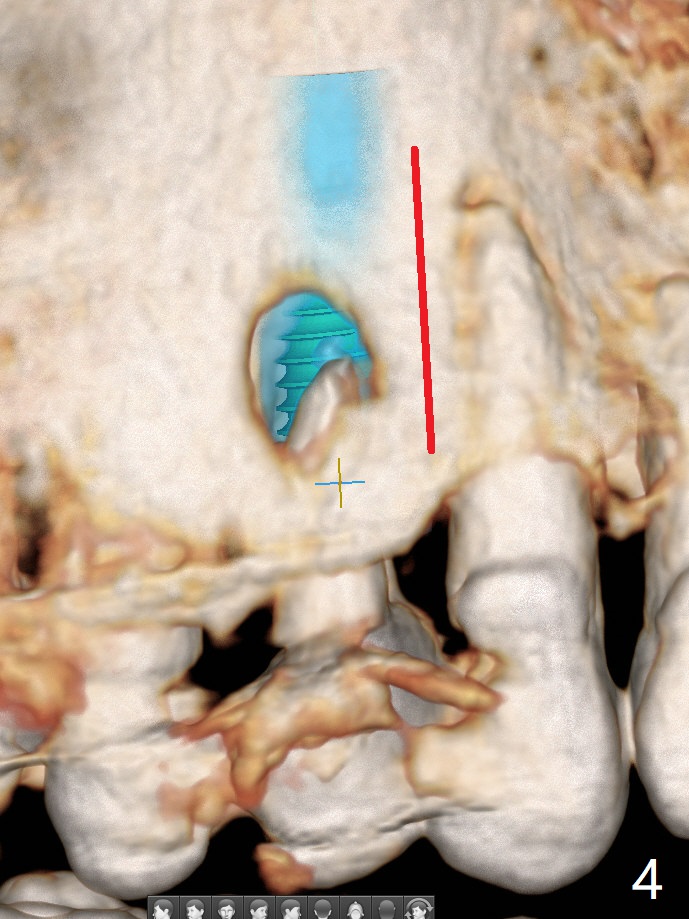

A 74-year-old woman is concerned about buccal fistula of the tooth #5 (Fig.1,2 >). It seems to be safe to place an immediate implant without too much possibility of developing periimplantitis in the future (Fig.3). With guide, restoration could be finished with a 15 degree angled abutment. Remove granulation tissue from the buccal fistula and from the socket. Place a piece of PRF membrane externally (tunnel incision, Fig.4-6 red line) or internally (from the socket) before bone graft (before and after implant placement (Fig.5,6 yellow circles)). Take 5x5 cm CT immediately postop to confirm the repair.